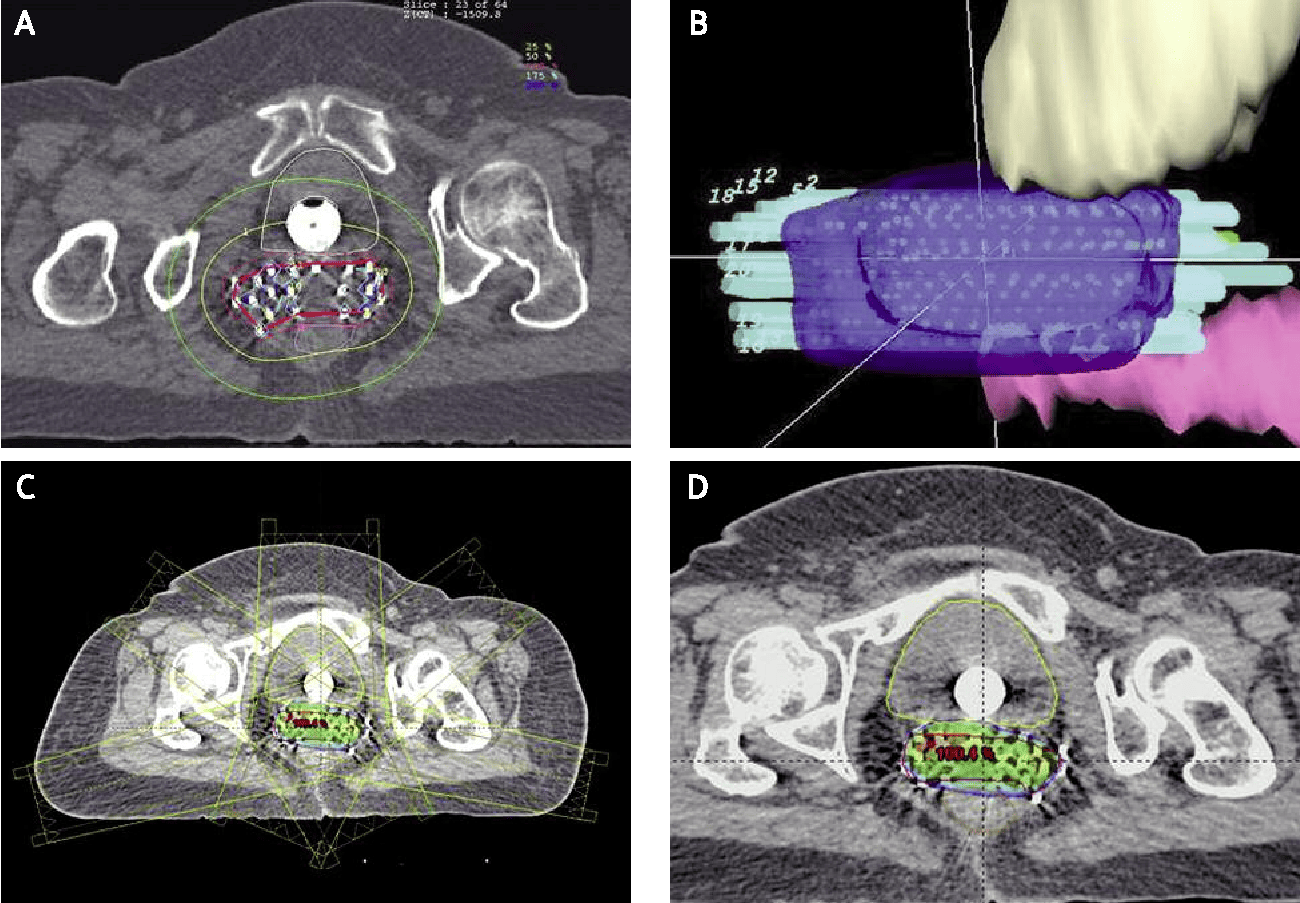

Interstitial brachytherapy is a type of internal radiation therapy where radioactive sources are placed directly into the tissue of the tumor, rather than inside a nearby body cavity (like in intracavitary brachytherapy).

Involves inserting needles, catheters, or radioactive seeds directly into or around the tumor.

Radiation is delivered from within the tissue, allowing for a high dose to the tumor with minimal exposure to surrounding healthy tissue.

Useful for irregularly shaped or deeply located tumors